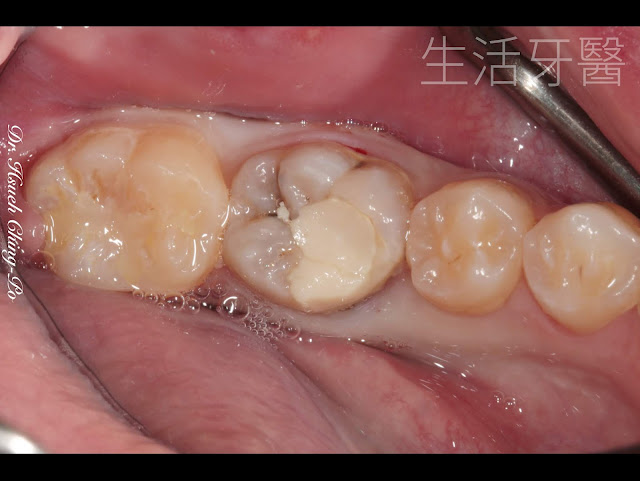

患者左下第一大臼齒近心舌側崩裂

除了上面有臨時填補物之外

還可以觀察到有其他黑色蛀牙的區塊

舌側觀